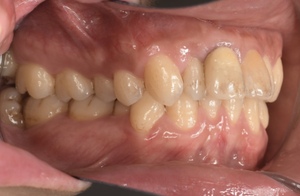

CASE 14

下顎before

下顎after

臼歯before

臼歯after

基本情報

| 年齢・性別 | 27歳・男性 |

| 主訴 | 歯石とりたい |

| 治療内容 | スケーリング |

| 治療期間 | 30分 |

| 治療費 | 約1,500円(保険診療) |

| リスク・副作用 | 知覚過敏、歯肉退縮、出血 |

| 治療方針 | 歯列不正でプラークがつきやすいため、TBIを行い定期的に歯石を除去していきます。 プラークコントロールが出来るようになったら定期検診でクリーニングを行っていきます。 |